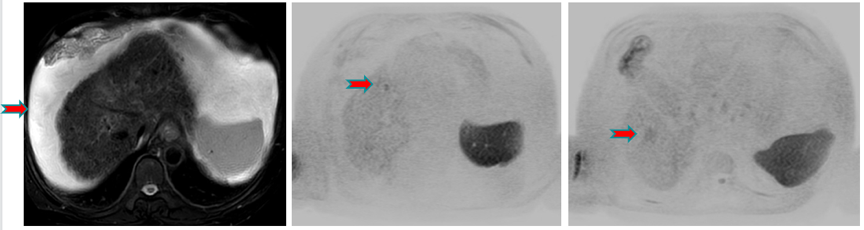

患者系原发性肝癌,肝硬化多年,中国肝癌分期(CNLC)Ⅱb期,2020年6月行经导管肝动脉化疗栓塞(TACE)治疗,术中行肝动脉造影示肿瘤供血不丰富,给予碘化油及明胶海绵栓塞,术后碘油沉积欠佳,术后给予仑伐替尼8mg qd靶向抗肿瘤治疗。术后1个月MRI显示,DWI信号明显增浓;术后2个月、3个月和4个月复查MRI,DWI信号明显增浓,肿瘤一直存在,较前变化不显著(图2)。

图2.介入术后1个月、2个月、3个月和4个月复查MRI